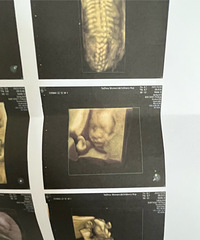

预产期:2023年5月20日建卡医院:温岭市妇幼保健院产检医院:温岭市妇幼保健院胎宝宝小名:还没取呢生产医院:未定哦B超照片/孕期相关照片一张